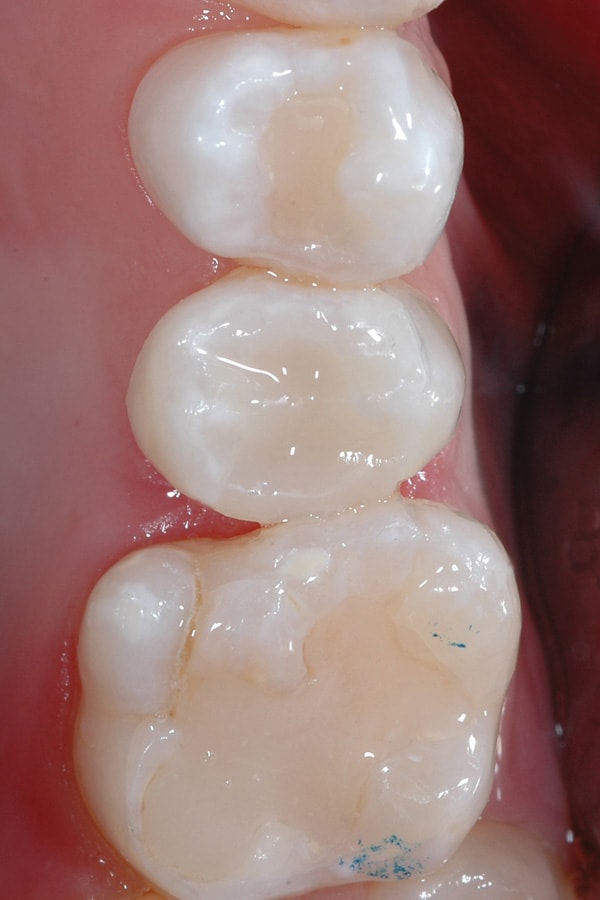

An initial layer of SureFil SDR flow was placed into the preparation, followed by a 20-second light-cure (Figure 7 and Figure 8). TPH Spectra High-Viscosity shade A2 was packed into the preparation and cured in 2-mm increments (Figure 9 and Figure 10).

The final restoration was finished with fluted composite burs and polished with Enhance and PoGo (Figure 11). The final radiograph of the restoration shows high radiopacity of the resin restorative materials and no junction can be discerned between the flowable and restorative materials (Figure 12).